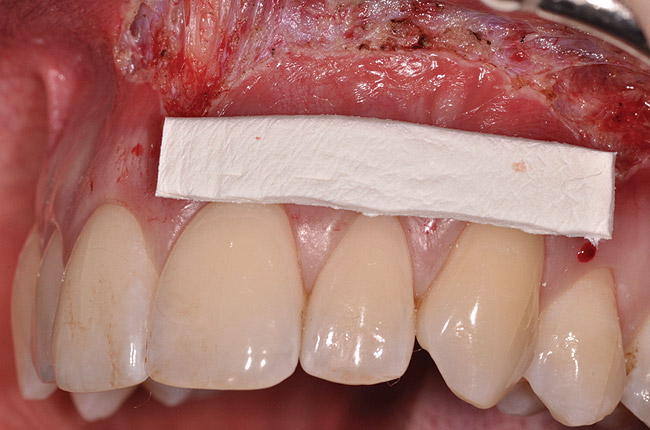

Fig 8. Dermis selected, and sized for defect.

Figure 8